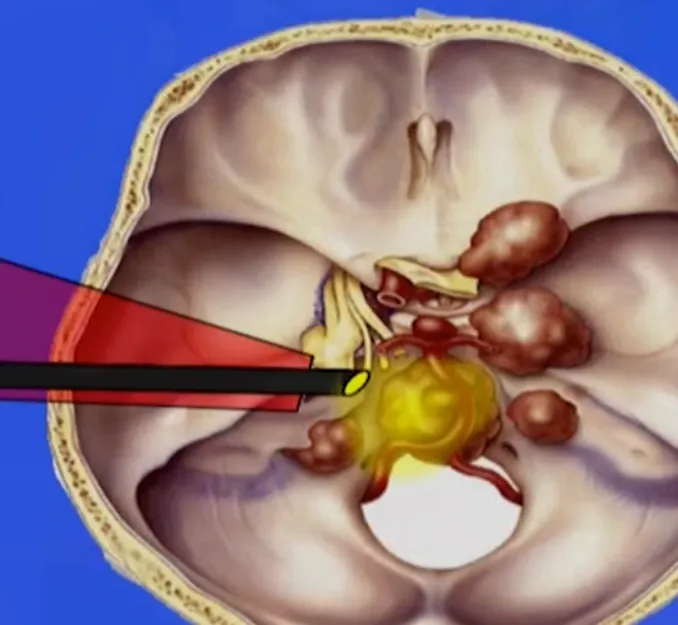

本例手术采用岩前入路,通过前岩骨解剖结构吸除肿瘤,因肿瘤位置较低(低于内听道水平)。

手术重点关注两个方面:降低脑脊液漏风险和保护外展神经(CNVI)。福教授将内镜作为手术第二部分,用于切除肿瘤下部和区分外展神经。患者围手术期出现外展神经功能暂时性受损,但很快恢复,后续能继续从事司机职业——这也是福教授治疗该患者的首要目标。此外,该患者未出现脑脊液漏并发症。